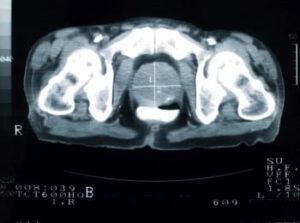

This MRI of a man’s pelvis shows that his prostate is enlarged to almost three times the regular size, which may be a sign of cancer. The prostate is marked by a cross.